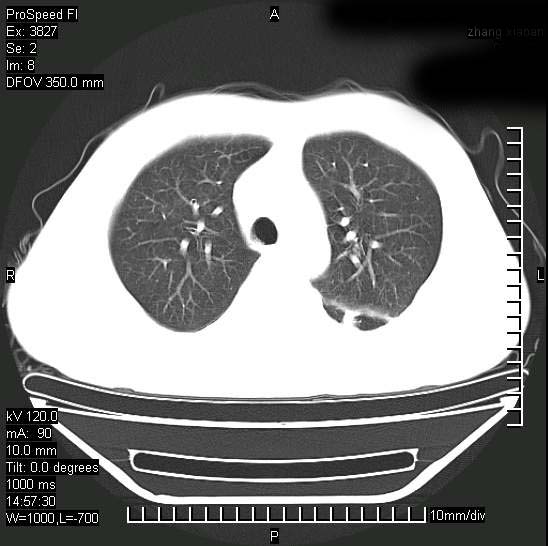

男性,一月前出现右侧肋区疼痛,较剧烈,干咳,无发热,自诉使用抗炎药后缓解,几天前又出现左侧剧烈疼痛,

发热,体温38。9,今天ct,考虑左侧包裹性脓胸,胸腔积液,右上中肺小斑片影,结核/炎症?胸水未见恶性细胞。